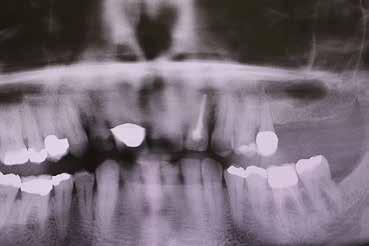

A korai harmicas éveiben járó hölgy rendelőnkbe érkezésének oka a jobb felső nagymetsző fog bizonytalan érzkenysége, elmondása alapján gyermekkorában trauma érte a felső frontrégiót. A frakturált klinikai koronákat kompozittöméssel helyreállították, egyéb kezelést akkor nem tartottak szükségesnek. Az utóbbi hónapokban tapasztalt érzékenység miatt kereste fel rendelőnket. A klinikai vizsgálat (1. és 2. kép) és a CBCT felvétel (3. kép) alapján diagnosztizált külső gyökérreszorpció megoldására a fog eltávolítását, implantátum

bukkális 1. kép: Kiindulási állapot, 2020. január. 3. kép: Kiindulási CBCT felvétel. 2. kép: Kiindulási állapot a palatinális oldal felől.